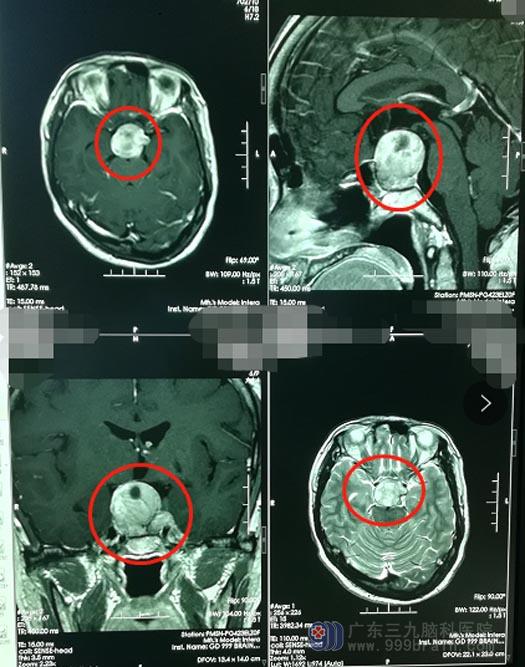

55岁的朱阿姨2年前出现视物模糊,在当地医院就诊,头部MR检查考虑垂体腺瘤,予以“鞍区垂体腺瘤切除术”。最近朱阿姨回医院复查,提示垂体腺瘤复发了。

术前准备妥当后,由鲁明主刀在全麻下行“内镜经鼻蝶鞍区复发垂体大腺瘤切除术+颅底重建术”;手术顺利,术中,朱阿姨生命体征平稳,术后神志清醒、病情稳定。复查提示肿瘤已全切。